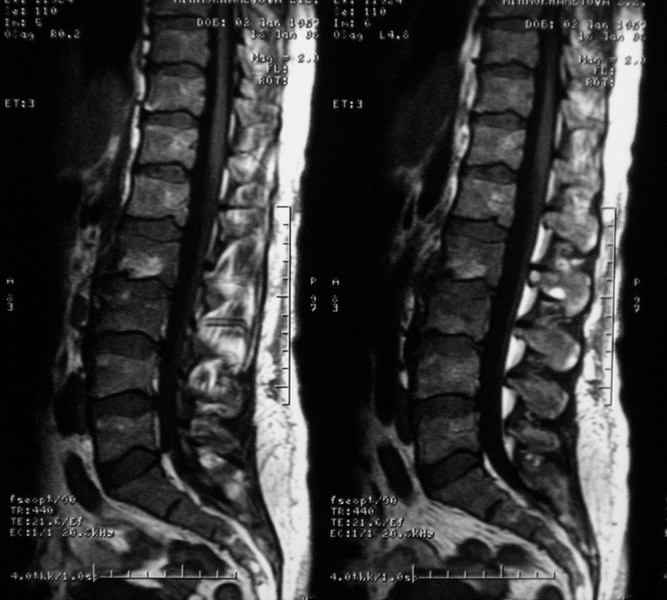

Отправляю MRI в динамике, снятые с пленки на фотоаппарат.

|

MRI через три недели

По данным представленных КТ и МРТ у больной имеется достаточно выраженная степень деструкции тел позвонков (около 30% общей костной массы тела позвонка), что определяет высокий риск возникновения патогических переломов и появления локальной кифотической деформации на этом уровне.

Данные МРТ выкладываешь некорректно - это не "контроль в динамике", а поход по Сусанинским местам, сравниваемые срезы за разные даты должны быть одинаковыми.